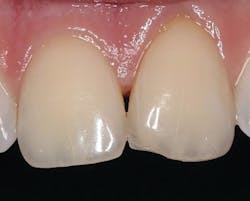

A 28-year-old male fractured the mesial-incisal of tooth no. 9 in a sporting event (figure 5). The tooth was asymptomatic, and no anesthesia was necessary. A 2–3 mm irregular-shaped bevel was prepared using a very fine diamond (45u) with an emphasis on a heavier bevel at the fracture margins and feathering to an infinite bevel approach away from the fractured portion. This not only helps to give the composite more surface area to bond to, but it also creates sufficient thickness to hide the fracture line and allow the material to optically blend into the surrounding tooth structure. After isolation with a Mylar strip, a total-etch technique was utilized followed by Tokuyama Universal Bond. Since the incisal fracture possessed both dentinal shading and a highly translucent enamel component, a two-step approach was implemented for the restorative phase. An increment of the Omnichroma resin was expressed and shaped to mimic the dentinal mamelon effect, and then cured for 20 seconds from the labial and lingual with an LED light. A layer of a translucent composite (Estelite Omega Trans, Tokuyama Dental America) was placed over the cured Omnichroma to give the desired enamel result. After light-curing, interproximal finishing was obtained with a composite strip system (ContacEZ), and occlusion was verified. Shaping was accomplished with the 12 fluted carbides and polished with the abrasive cup and points (figure 6).About the Author